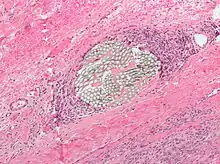

- Tissue reactivity: inflammatory response of the surrounding tissue that can cause materials to break down quicker and lose tensile strength. Non absorbable synthetic suture have the lowest of tissue reactivity, while the absorbable natural fibers have the highest rates of tissue reactivity.[4]